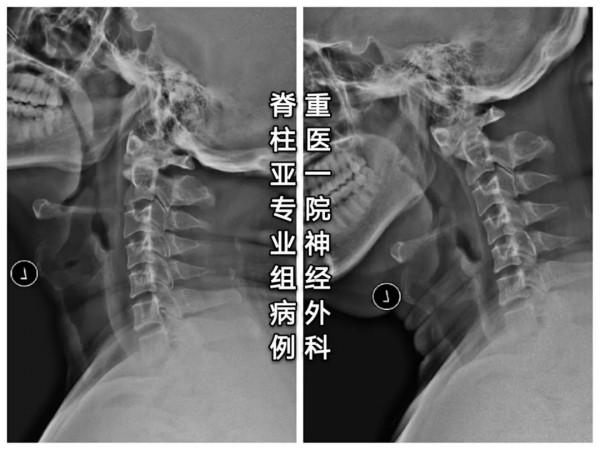

治療:手術復位固定

- 面對椎動脈高跨,“小心假設,大膽求證”,總能找到合適的釘道。

- 本例選擇靠近C1-2小關節的上關節面和靠近C2峽部內側的位置建立釘道。